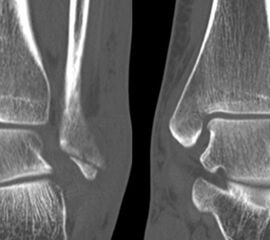

Liegt eine Fraktur des oberen Sprunggelenks vor, ist sowohl zur Entscheidung für ein konservatives oder operatives Vorgehen, als auch zur Operationsplanung, ein ausreichendes Verständnis der Fraktur und ihrer Morphologie notwendig. Insbesondere bei komplexen Verletzungen ist dafür die konventionelle Röntgenaufnahme in vielen Fällen nicht ausreichend. So konnten z.B. Black et al. zeigen, dass die operative Strategie zur Versorgung von OSG-Frakturen in 24% basierend auf einer zusätzlichen CT-Bildgebung relevant geändert wurden 7. Dies betraf die Lagerung, die Wahl des Zuganges und die Art der osteosynthetischen Versorgung. Besonders häufig änderte sich das Vorgehen bei Verletzungen des medialen (21%) und des posterioren Malleolus (15%). Darüber hinaus führten dislozierte (dislozierte Frakturen 31% vs. nicht-dislozierte Frakturen 20%) oder komplexe Frakturen (Trimalleolar-Frakturen 29% vs. Unimalleolar-Frakturen 10%) besonders häufig zu relevanten Änderungen des operativen Vorgehens. Die Computertomographie ist daher, insbesondere bei Bi- und Trimalleolar-Frakturen, essentiell für das Verständnis der Fraktur und somit für die Planung und Durchführung der Operation. In Abbildung 4 und 5 sind exemplarisch ein Röntgen- und ein CT Befund gegenübergestellt.